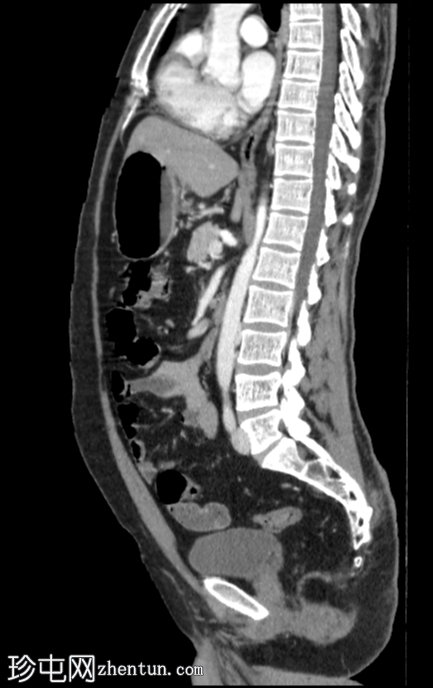

CT

矢状位增强扫描(门静脉期)

CT扫描显示右肾上半部可见一部分边界清晰的肿块,其密度成分包含软组织和脂肪。

其余腹腔脏器未见明显异常。

可见累及L4椎体的血管瘤。

目前的CT

影像

学表现为右侧肾血管平滑肌脂肪瘤,无内部出血。